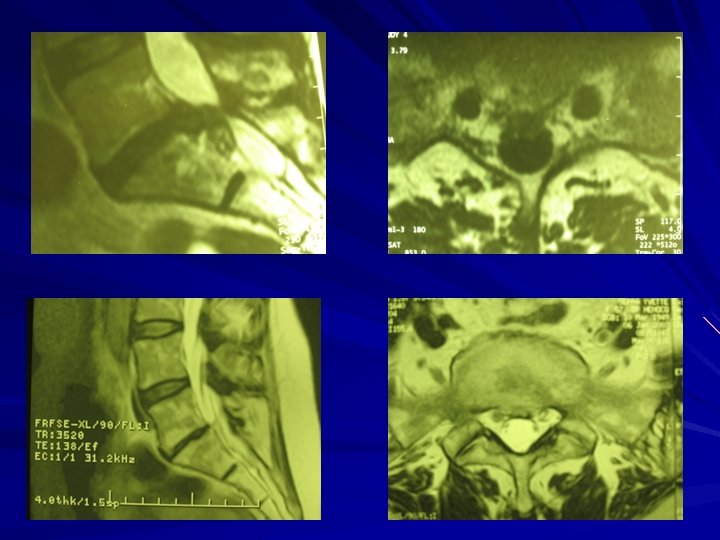

IMPERATIF en cas de sciatique PARALYSANTE Doit rester le dernier recours Sciatique très douloureuse (jour et nuit) et résistante au traitement médical L’Imagerie (Scanner, IRM) doit concorder avec les symptômes HERNIE DISCALE LOMBAIRE CANAL LOMBAIRE ETROIT (Arthrose) AUTRES CAUSES (Neurinomes)

Canal lombaire étroit Elargissement du canal lombaire Risques et suites idem que pour la hernie discale lombaire Peut être associé à une hernie discale lombaire

RESULTATS Hernie discale d’effort de l’adulte jeune -90 % de bons résultats 85 Canal lombaire étroit arthrosique 80 % 75 - Discopathies étagées (plusieurs étages), travailleur de force, accidents du travail 50 -60 %